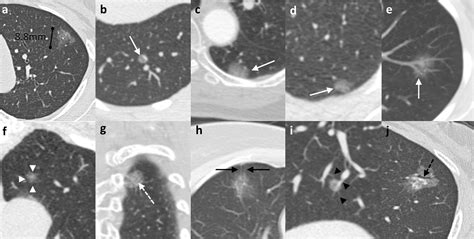

Most cases of AAH are hear in individuals undergoing screening for other conditions, such as continuing hindering pulmonary disease (COPD) or follow-ups for smoking chronicle. Because AAH nodules are typically very small - usually measure less than 5 millimeters in diameter - they are often hard to see on standard X-rays and are most ofttimes identify using high-resolution computed imaging (HRCT) scans.

One of the chief challenge in thoracic medicine is differentiating Atypical Adenomatous Hyperplasia from other character of nodules. Diagnostician and radiotherapist use specific standard to ensure an precise diagnosing. The undermentioned table provides a quick reference to differentiate mutual pulmonary findings:

When a physician identify a likely instance of Atypical Adenomatous Hyperplasia, the strategy is normally centered on "sleepless waiting". Because these lesions are super slow-growing, perform a biopsy on every small nodule can be more harmful than the wound itself. Rather, doc utilize sequent HRCT scan to supervise the tubercle's sizing and density over month or years.

• Constancy: If the tubercle remains unaltered in size and appearing, it is frequently keep under reflection.

• Increase: Any substantial increase in the size of the tubercle may activate further diagnostic testing, such as a PET scan or a biopsy.

• Solidification: Modification in the "ground-glass" concentration of the nodule (where it turn more solid) can be a signaling that the lesion is advance toward an invading province.